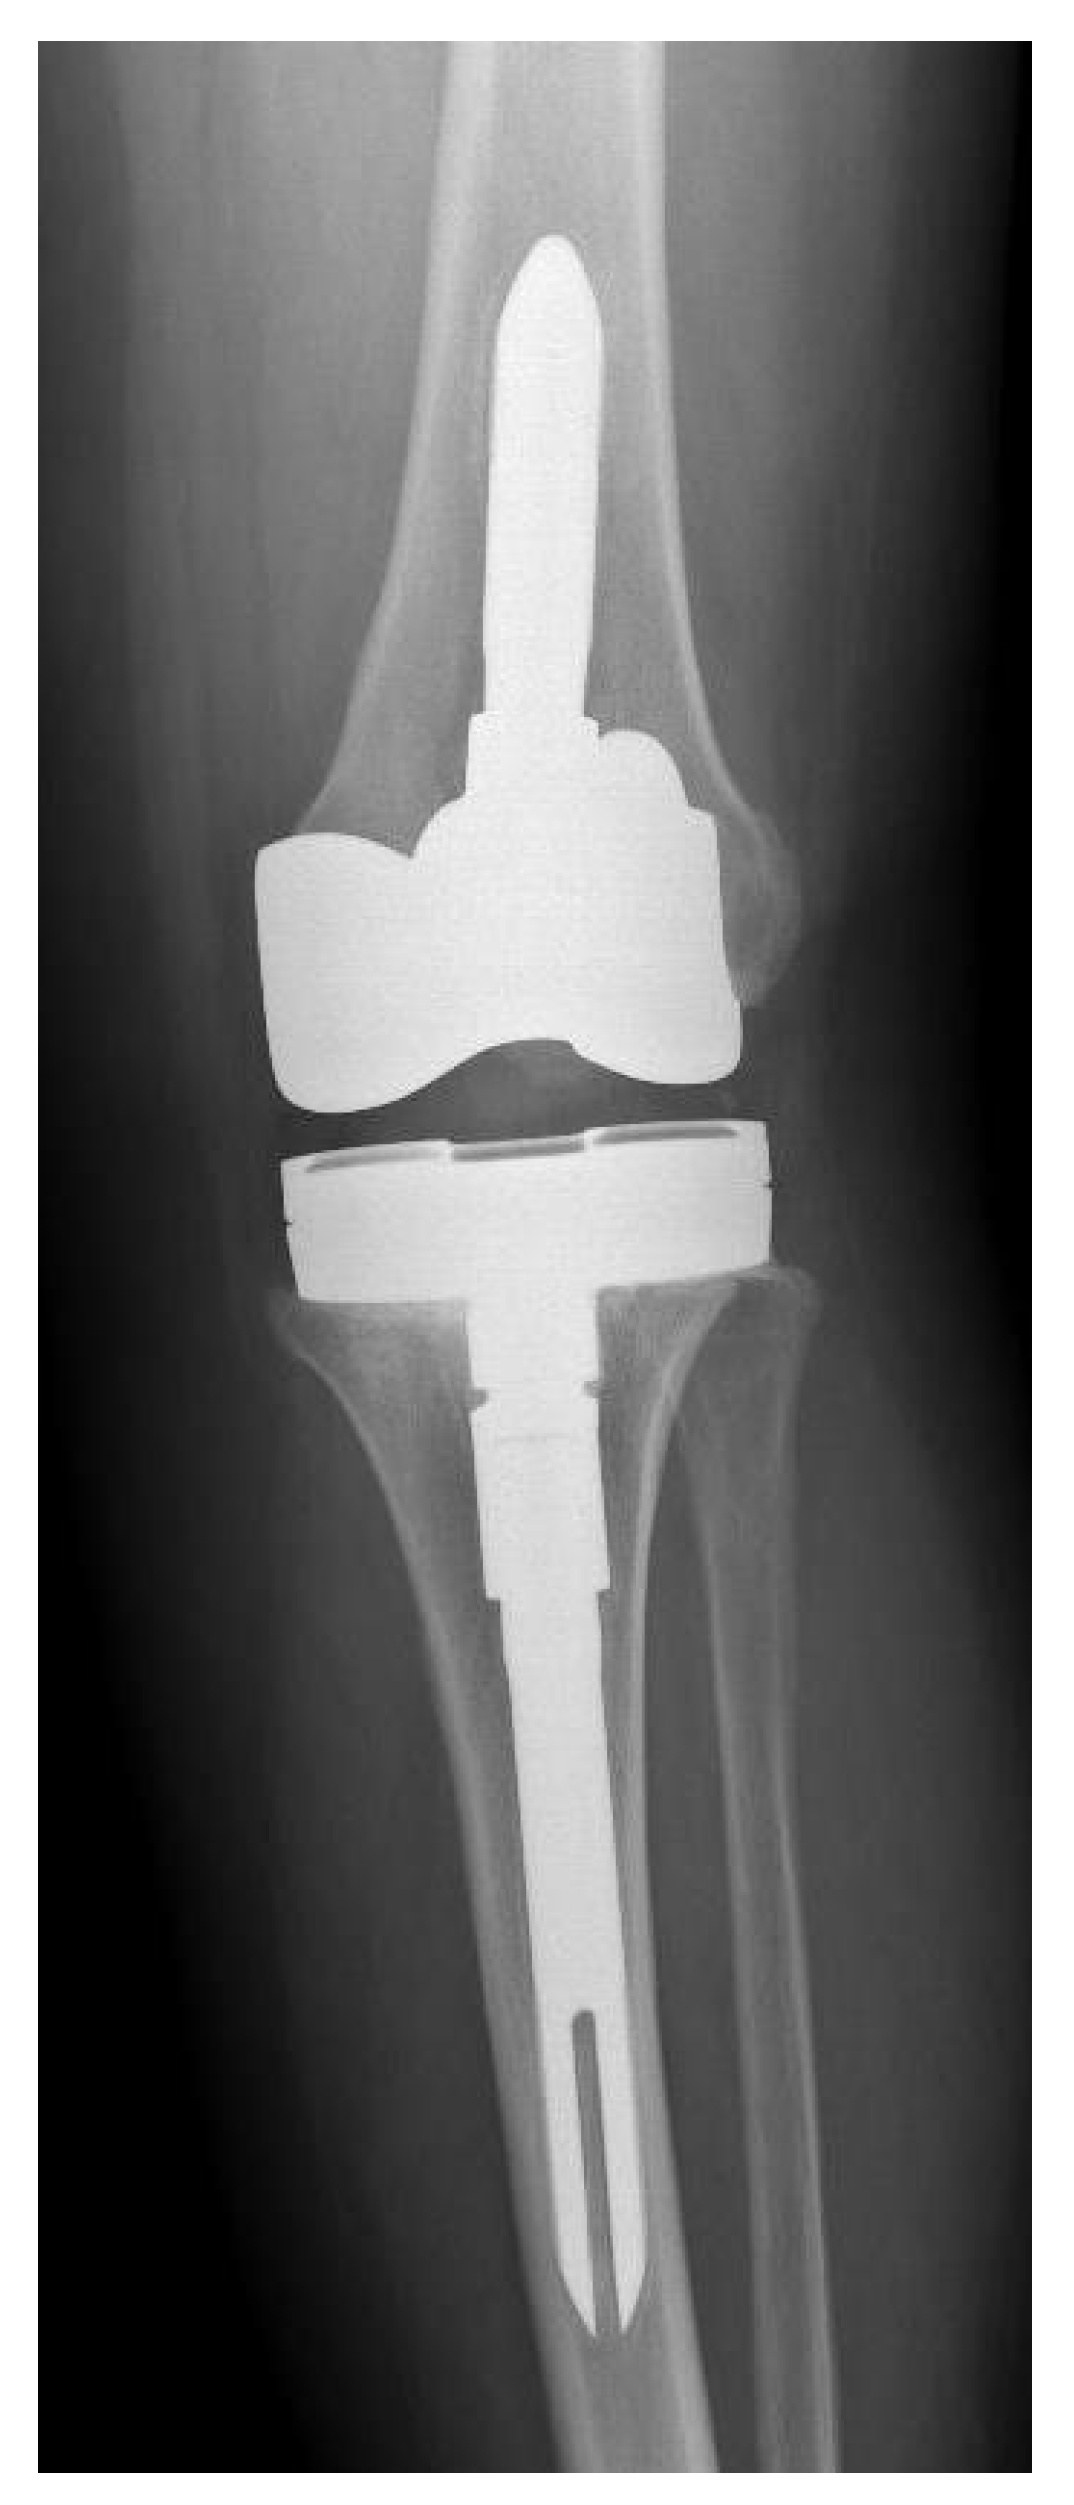

Figure 2. Postoperative X-ray of new knee prosthesis of patient number 5.

The cost for treating these 18 patients using 1-stage revision, according to the cost criteria described by Srivastava et al. [17], totaled USD 435,186 (18 patients × USD 24,177 per patient). Added to this cost are the costs of the six surgical complications occurring in five patients: two acute debridements (USD 17,723 per patient = USD 35,446), one aseptic revision (USD 24,177 per patient), one tendon repair (USD 24,177 per patient), one closed reduction (USD 24,177 per patient) (Figure 1 and Figure 2), and one neuroma excision (USD 24,177 per patient). The total cost for treating these 18 patients using a 1-stage revision amounted to USD 567,340. If these patients had been treated using 2-stage revision, the costs would have totaled USD 858,492 (18 patients × USD 47,694 per patient) without any complications. Therefore, the total economic savings for our hospital for these 18 patients was USD 291,152.